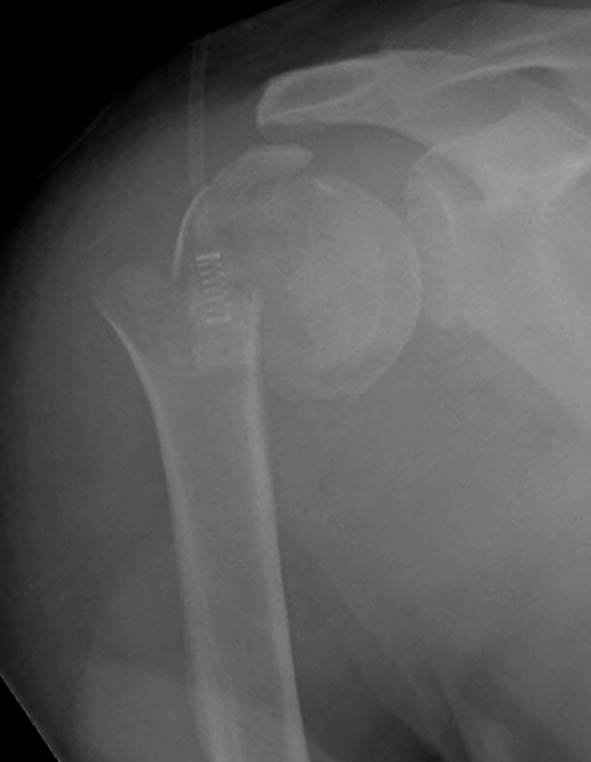

Наш недавний случай перкутанной фиксации "методом

Сиэтла" спицами 2.8 мм с резьбой на конце.

Головка плечав небольшом варусе или это проекционное?

-Головка плеча в небольшом варусе или это

проекционное?

Да, там имеем небольшой варус, надеемся, что в будущем проблемы не будет.

Из-за большого обьема конечности доступ к бугорку был затруднен, предварительно зафиксированный шуруп не удержал бугорок, поэтому фиксацию провели толстыми нитками. Состоятельность фиксации бугорка обычно проверяем во время операции, под рентген контролем проводится движения конечности, особенно приведение.